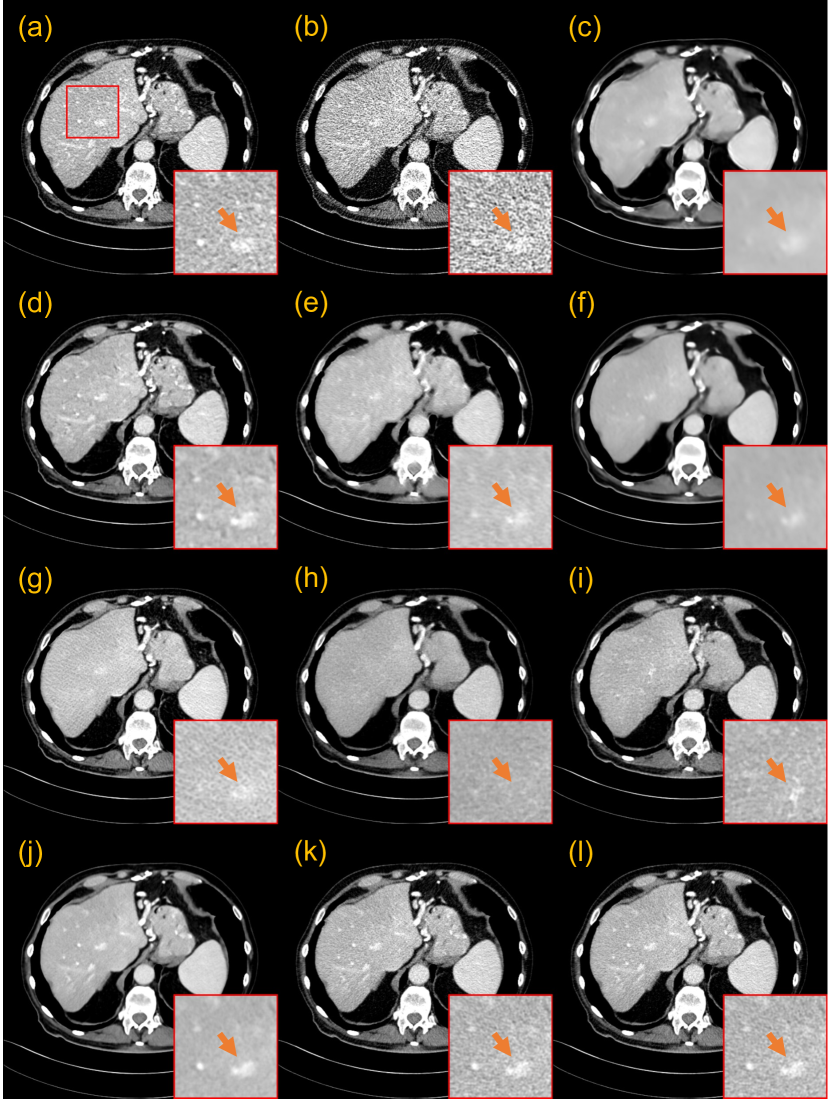

3.3.1 Evaluation on the 25% dose

Fig. 4 presents a representative slice of 25% dose test data denoised by different methods for visual comparison. The orange arrow indicates the location of the lesion in the red region of interest (ROI). Although the RED-CNN-based methods effectively remove noise from the LDCT image, it tends to blur fine details. Among the GAN-based methods, WGAN-VGG introduces velvet artifacts, and DU-GAN provides textures closer to NDCT images. CNCL-U-Net preserves the most details, but its residual map shows a noticeable difference in predicting the bone edge. Among the diffusion-based models, DDM2 exhibits obvious artifacts and CT number drift. We conjectured that this phenomenon may result from the fact that DDM2 assumes the image noise adheres to a Gaussian distribution, which deviates from the actual noise distribution of CT images. Both in terms of texture preservation and detail retention, IDDPM and our CoreDiff surpass other compared methods. For the IDDPM, lowering the number of sampling steps to 50 has little impact on the denoising performance. However, when is reduced to 10, the model produces the poorest results due to much insufficient sampling. In addition, IDDPM-1000/-50 erase the critical lesion information, while our CoreDiff retains them well. The residual map confirms that our approach has the least prediction bias.

Table 1 presents the quantitative results of all methods. Our CoreDiff outperforms all DL-based methods and the iterative reconstruction algorithm. Notably, our method outperforms the second-best method (PDF-RED-CNN) by a large margin in terms of all metrics.

Fig. 5 presents the qualitative results of 5% dose test data. In this ultra-low dose scenario, the FBP image suffers from significantly severe noise and streak artifacts due to the photon starvation effect, making it unacceptable for clinical diagnosis. The denoising performance of some denoising methods has a sharp decline. Fig. 5 shows that RED-CNN-based methods and CNCL-U-Net produce over-smoothed results. In addition, both PWLS and WGAN-VGG introduce noticeable artifacts to the denoised images. The DU-GAN obtains the best performance besides the diffusion-based methods. However, the denoising result of DU-GAN shrinks the lesion size. Other diffusion-based models, except for IDDPM-10 and DDM2, consistently exhibit remarkable performance in ultra-low-dose denoising tasks, showing great promise for LDCT denoising. Among them, our CoreDiff exhibits the best denoising performance both in terms of residual maps and zoomed-in ROIs. Furthermore, Fig. 6 shows the profile results of the different methods, as indicated by the blue line in the NDCT images in Fig. 5. The red arrow indicates that our CoreDiff maintains the CT number better than other methods.

Table 2 presents the quantitative results of 5% dose test data. Our CoreDiff also surpasses all competing methods. On average our CoreDiff achieves around +1.46 dB PSNR, +1.39% SSIM, and -15.45% RMSE over the second-best PDF-RED-CNN. In addition, Table 2 also reports the computational time of denoising a single image by different methods. The inference speed of the CoreDiff is much faster than that of diffusion-based models, which has reached a clinically acceptable level.

In addition, we incorporated the contrast-to-noise ratio (CNR) [57, 58] to assess the detectability of low-contrast lesions in Figs. 4 and 5. The higher the CNR between the lesion and the background ROIs, the increased probability of detecting low-contrast lesions. As shown in Fig. 7, we carefully selected the blue lesion ROIs and the yellow background ROIs from two slices, and the CNR values for ROIs denoised by different methods are presented in Table 3. It can be observed that both RED-CNN and PDF-RED-CNN achieve the top two CNR values, while our method ranks third. Nonetheless, as depicted in Fig. 7, both RED-CNN and PDF-RED-CNN blur the edges of lesions, which is important for doctors in staging the disease and determining its benign or malignant nature. Considering that CT numbers are often used to differentiate healthy tissues from diseased ones in many clinical practices, we also calculated mean pixel values of lesion ROIs in Table 3. Notably, our CoreDiff demonstrates the CT number of the lesion ROI closest to the ground truth.